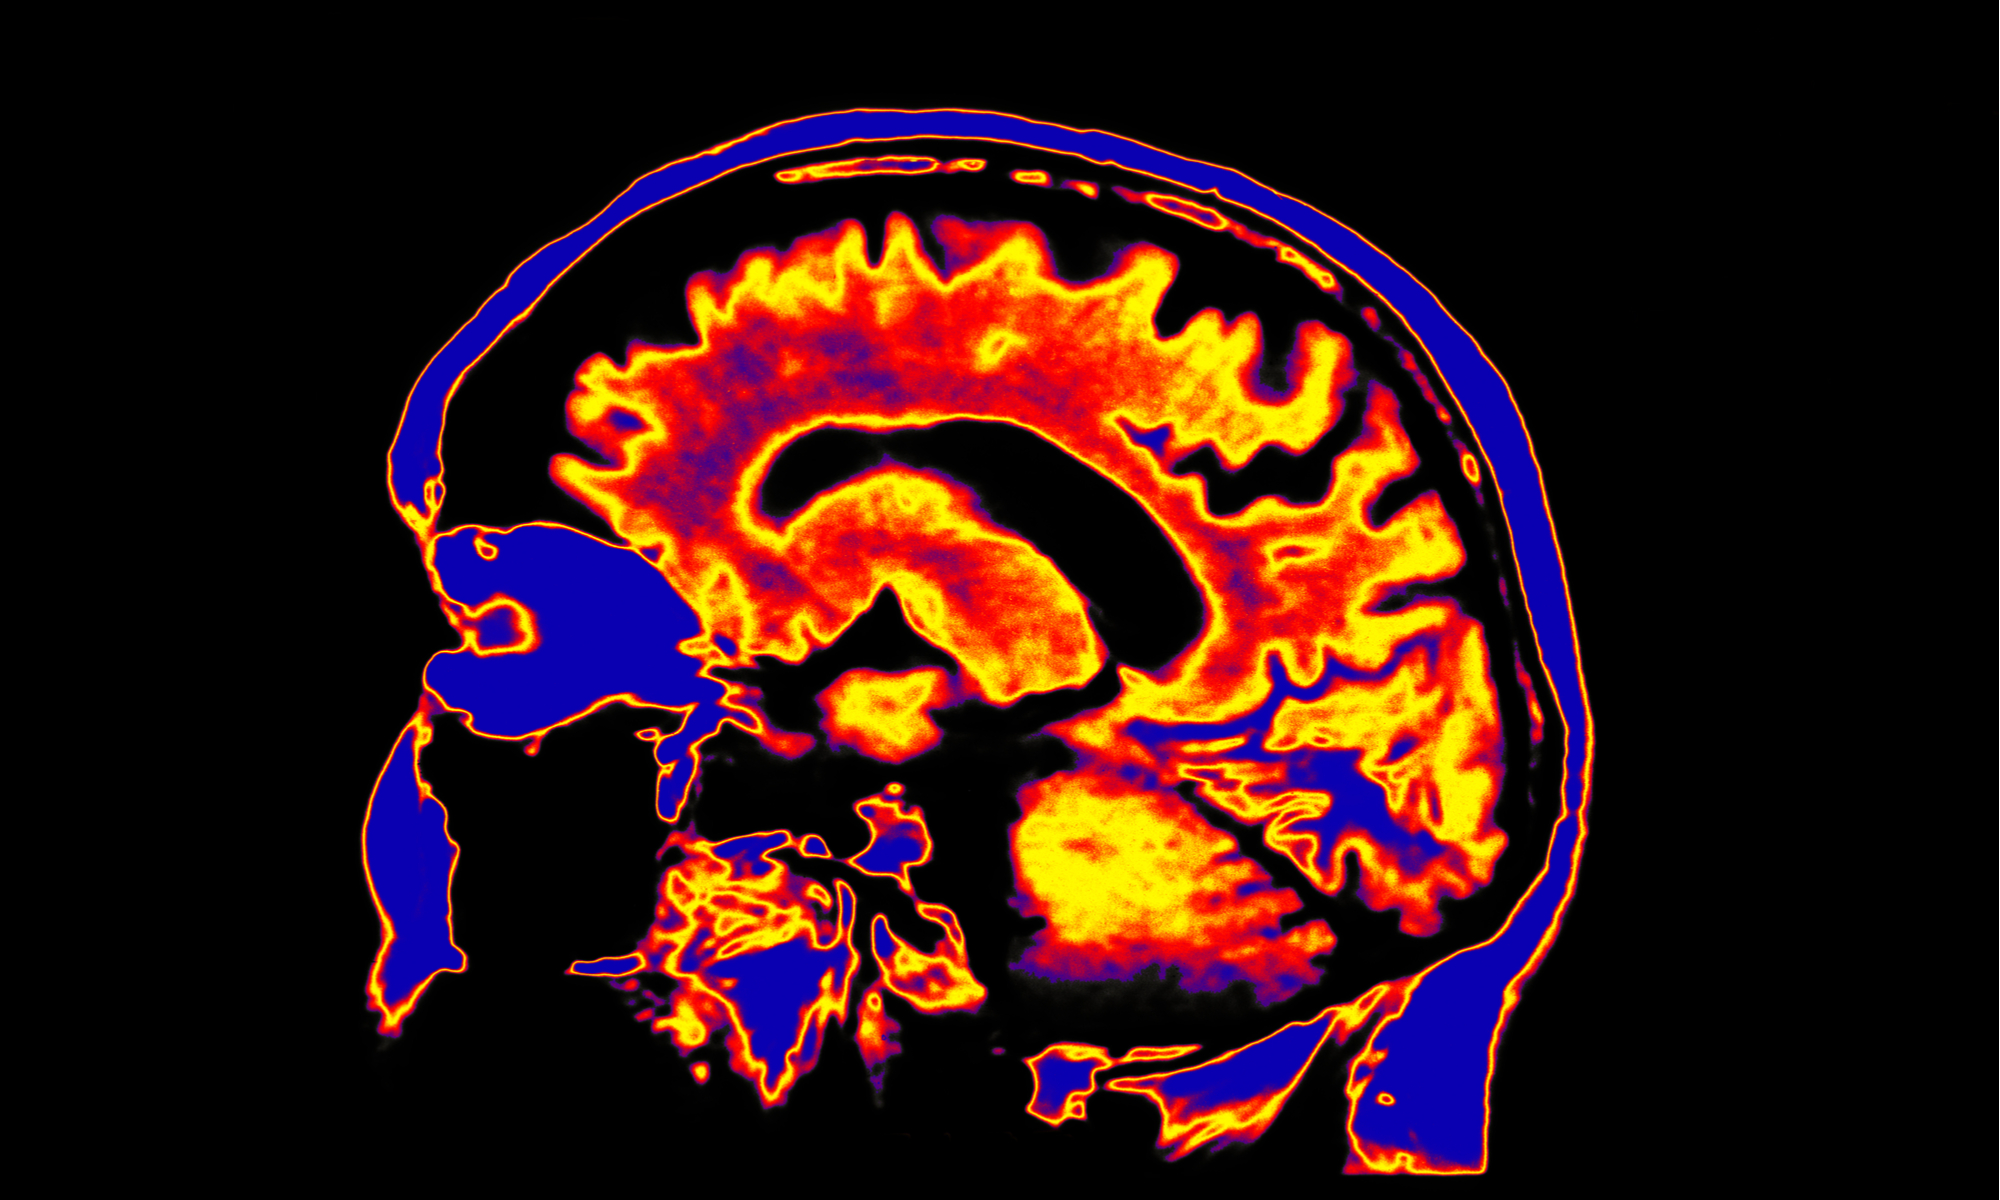

Human consciousness is one of the grand mysteries of our time on earth. How do you know that you are “you”? Does your sense of being aware of yourself come from your mind or is it your body that is creating it? What really happens when you enter an “altered” state of consciousness with the help of some chemical or plant? Are animals conscious? While you would think this basic enigma of our self-awareness would be at the forefront of scientific inquiry, science does not yet have strong answers to these questions.

One way to think of consciousness is to conceive of it as a byproduct of numerous computations that are happening in your brain.

The integrated information theory, created by neuroscientist Giulio Tononi of the University of Wisconsin-Madison, proposes that conscious experience is an integration of a great of amount of information that comes into our brain, and that this experience is irreducible. Your brain interweaves a sophisticated information web from sensory and cognitive inputs.

The global workspace theory of consciousness, developed by Bernard Baars, a neuroscientist at the Neurosciences Institute in La Jolla, California, says that maybe consciousness is simply the act of broadcasting information around the brain from a memory bank.